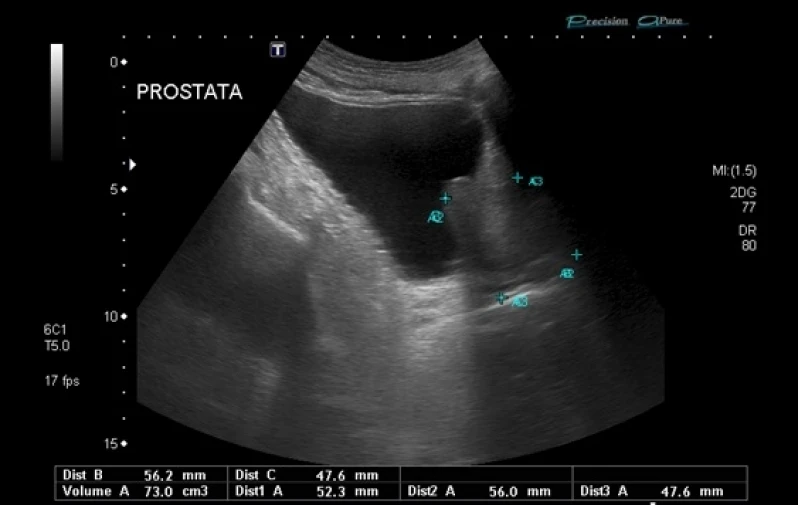

Biópsia Prostática de Saturação

A biópsia prostática de saturação é indicada quando após exames laboratoriais e avaliação clínica o médico urologista suspeita da presença de um câncer de próstata. No procedimento é retirado uma pequena amostra do tecido de um orgão, onde é feita uma avaliação microscópica em busca de encontrar doenças.